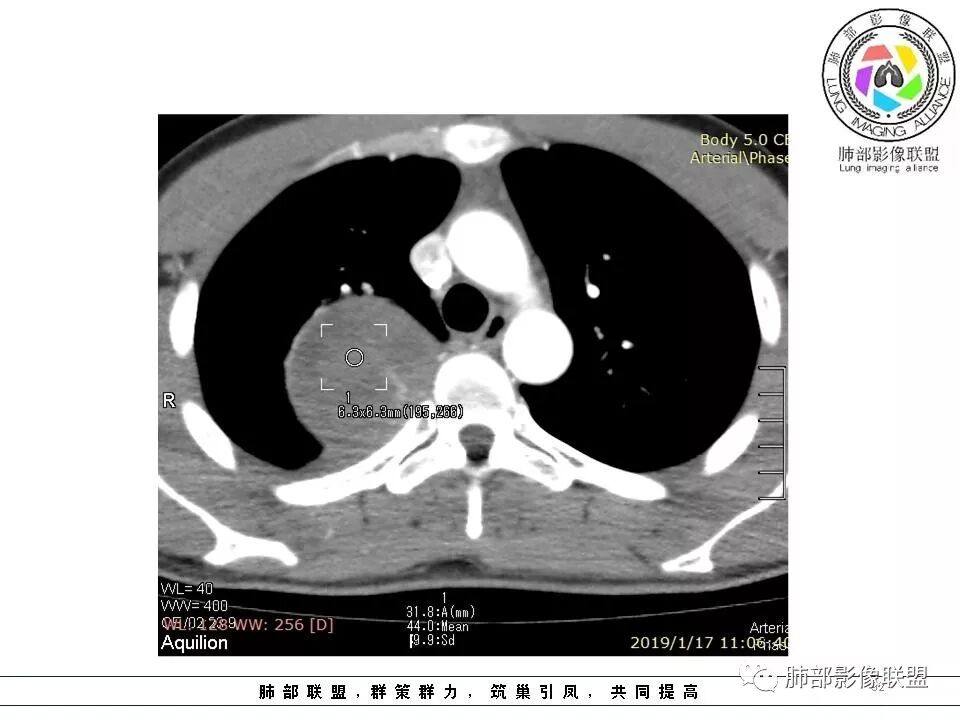

右后纵膈脊柱旁软组织占位,形态规则类圆,边缘光整,肺组织受压,胸膜尾,肋间动脉供血。中度不均匀延迟强化。

后纵隔脊柱旁占位性病变,疾病谱有神经鞘瘤,sft,节细胞瘤,髓外造血。此例有胸膜尾征,蛇纹征 ,延迟强化。考虑胸膜孤立性纤维瘤。看到有供血动脉,但不知道是哪里的血管。

后纵隔类圆形新生物,边缘光滑,胸膜尾征明显,贴近脊柱,蛇纹,血供丰富,考虑后纵隔软组织肿瘤,具体类型看不出来,鉴别神经鞘瘤。

右后纵膈脊柱旁软组织占位,边界清晰,光整,肺组织受压。胸膜被掀起,肋间动脉供血,中度不均匀延迟强化。考虑神经鞘瘤,不除外纤维瘤

右后纵膈脊柱旁软组织影,与纵隔结构分界不清,形态规则类圆,边缘光整,肺组织受压,胸膜尾,肋间动脉供血。肺动脉推移,中度不均匀延迟强化。考虑神经来源,神经鞘瘤,神经纤维瘤二者不易鉴别。

青年男性,间断胸痛;右侧脊柱旁可见一类圆形软组织密度影,密度欠均匀,增强扫描呈轻中度持续强化,邻近肺组织及肺动脉推移,可见肋间动脉供血,部分胸膜下脂肪可见,部分层面似见与右侧椎间孔相连。考虑后纵隔神经源性肿瘤。

1.右上胸内脊柱旁类圆形肿块,质地似乎比较坚实,密度稍显不均,但未显示明确的坏死。

如此密度形态的病灶位于肺边缘首先应当想到孤立性纤维瘤,可相邻胸膜未见明显的异常强化和胸膜方向延伸。

2.肋间动脉病供血也提示肿块来自后纵隔?

3.相邻椎间孔未见扩大,也未见块影延入椎管,易起自于神经根的鞘瘤似乎找不到支持点。

可惜未提供矢状位骨窗图像,如在肋骨内下缘观察到压迹有助于肋间神经的鞘瘤的判断,这是因为二者之间密切的毗邻关系。

4.静脉期轻度不均匀强化,注意不是环形强化,亦未见明确的“AB区”,这点也不支持神经鞘瘤。临床及病灶轻度强化都不支持副节瘤。